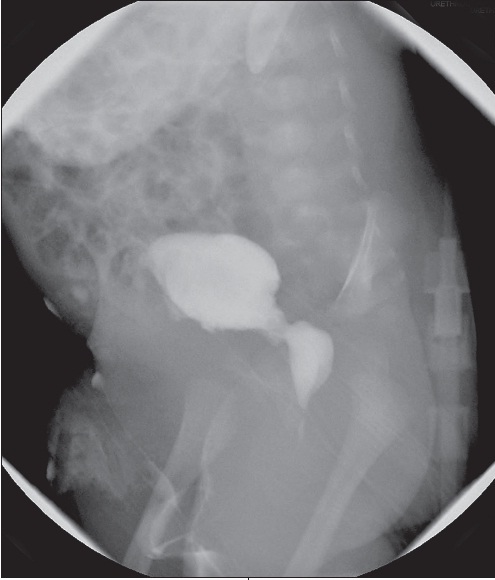

A voiding cystourethrogram (VCUG) was done: results are shown here.

ANSWER: POSTERIOR URETHRAL VALVES

The VCUG clearly shows posterior urethral valves (PUVs). The child had an impressive post-obstructive diuresis after a catheter was placed to bypass the obstruction. Several days later the urology team performed a cystoscopy and transurethral resection of the type I valves (at the 5, 7, and 12 o'clock positions). A catheter was left in place for 10 days, at which point the blood pressure, glomerular filtration rate, and levels of blood urea nitrogen and creatinine all normalized. The child is currently gaining weight and doing well.

PUVs usually appear at the earliest stage of urinary tract development. Consequently, the entire urinary tract develops in an abnormal environment of high intraluminal pressure from mechanical obstruction.3 Although 3 types of valves have been described, type I valves are found 95% of the time. This bicuspid valve radiates distally from the posterior edge of the midline prominence in the mid-prostatic urethra to the anterior proximal membranous urethra; the aperture varies to allow urine flow during voiding.3 The fused portion fills with urine and bulges into the membranous urethra, which gives the characteristic "sail-in-the-wind" finding commonly seen on VCUG (see Figure).4